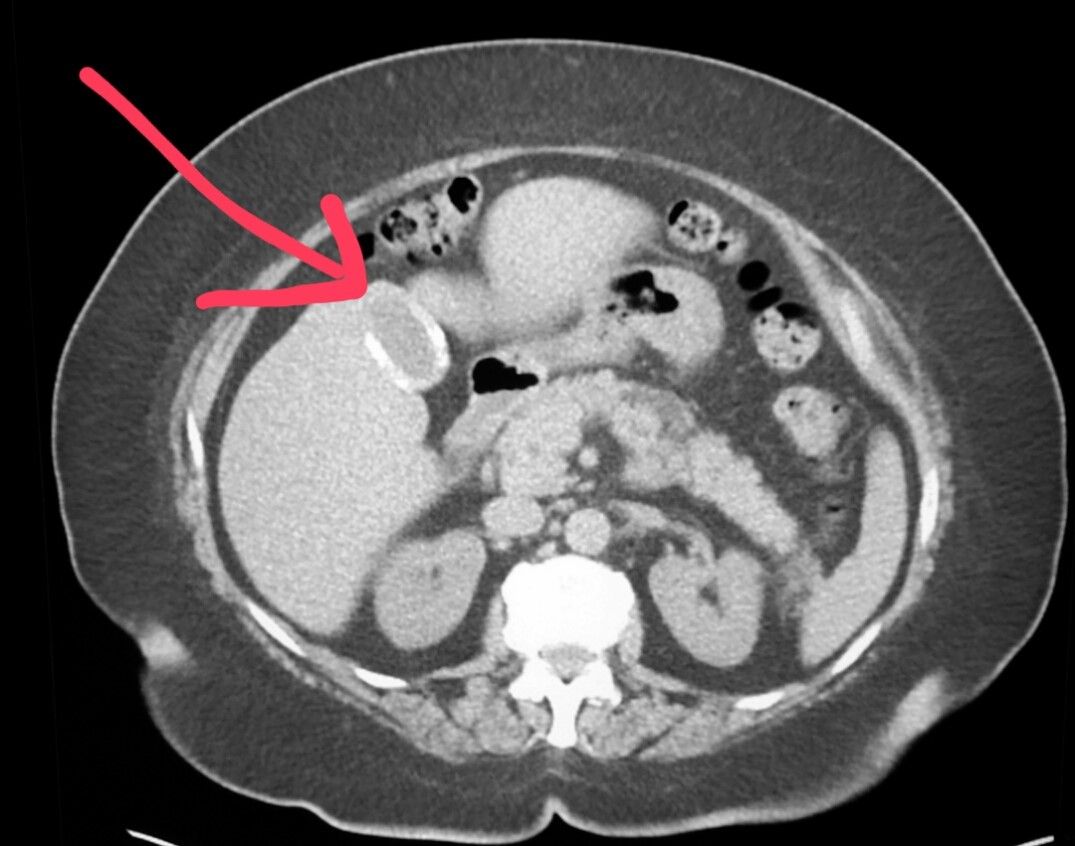

Computed Tomography (CT) scans have revolutionized medical imaging, providing detailed insights into the body’s internal structures. For gallbladder cancer detection, CT scans play a pivotal role in early diagnosis and treatment planning.

A CT scan utilizes X-rays and advanced computer technology to create three-dimensional images of the body. This non-invasive procedure offers a comprehensive view of the gallbladder and surrounding tissues, enabling healthcare professionals to identify abnormalities with precision.

During a CT scan for gallbladder imaging, multiple X-ray beams are directed at the patient’s abdomen from various angles. As these beams pass through the body, they’re absorbed differently by various tissues. The resulting data is processed by a computer to generate detailed cross-sectional images, or “slices,” of the gallbladder and surrounding areas.

You might have this test to look into your tummy (abdomen). CT scans can pick up a growth inside the gallbladder, or one that is growing outside the gallbladder.

CT scans are also helpful to see if the cancer has spread to the common bile duct, to nearby lymph nodes or to the liver.

A CT scan can create images of the pancreas, bile ducts, and gallbladder. Scans can reveal tumors, infections, and blockages, such as gallstones. The gallbladder is located in the upper right abdomen and sits just beneath your liver. It carries bile, which is important in the digestive process, as it helps break down fat.